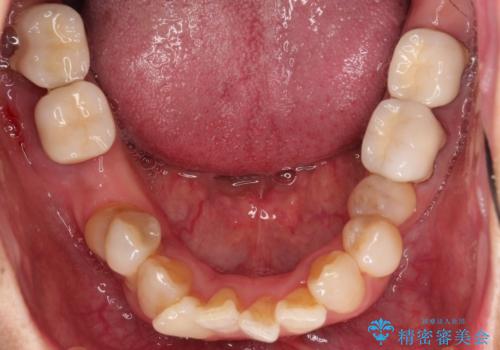

- 歯並びやグラグラする奥歯など、気になる所を全部治したいとのことで来院された患者様です。

奥歯は咬み合わせや歯周病により歯槽骨が失われていたり、むし歯や破折している歯などがあったりと、歯周病治療やインプラント補綴、矯正治療など、総合的に治療が必要と診断されました。

まずは歯周病治療やインプラント埋入を行い、環境が整った後にワイヤーを併用したインビザライン矯正を行い、オールセラミッククラウンにて補綴治療を行うこととしました。